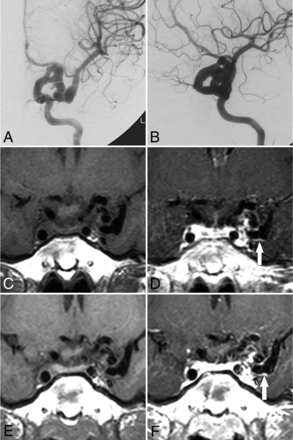

All patients had the unique feature, segmental elongation and tortuosity of the distal ICA, resulting in a tangled arterial mass (Fig 2). No differences were observed between the sides of onset (right, 11/20). Two patients presented with bilateral distal ICA dolichoectasia. In these 2 patients, we defined the side with more severe dolichoectasia as the ipsilateral side, while the other side was the contralateral side. The involved ICA segments ranged from segments 2 to 7, with a mean ± SD of 3.5 ± 1.6 segments. Fourteen patients had BA (n = 1) or ipsilateral PCA (n = 13) involvement [BA/PCA (+)]. We observed a significant correlation between ipsilateral A1, PcomA, BA/PCA, and midbrain hypoplasia and segmental ICDE of the distal ICA, unlike the contralateral side (Table 1).

Representative images of ICDE in a patient without PHACE syndrome (patient 6, a 28-year-old woman). A and B, Bilateral ICA angiography shows a tangled arterial mass of the left distal ICA and no observable left A1 segment. C, Left vertebral artery angiography shows a dolichoectasia of the left P1 and P2 segments (arrow). D, CT angiography shows hypoplasia of the left A1 segment (arrow). E, T2-weighted image of the brain shows hypoplasia of the left midbrain. F, CT image of vessel wall calcification in the left distal ICA (arrow).